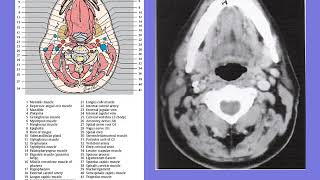

Ct Neck Anatomy

Ct Mri Neck Anatomy